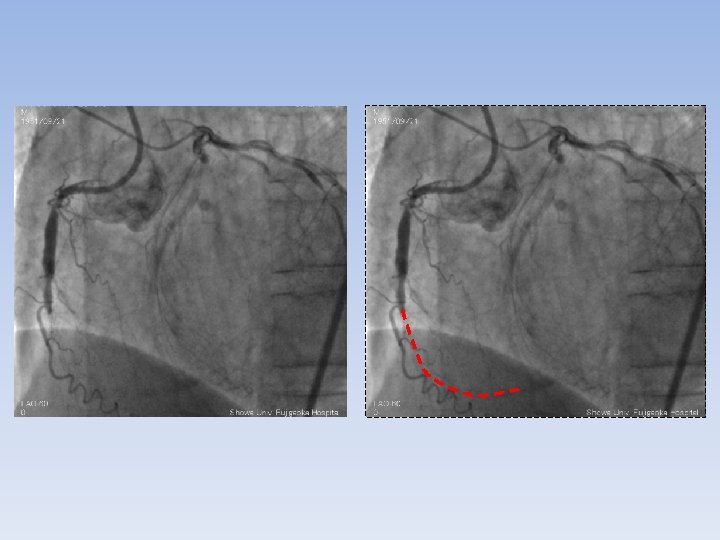

XT-R Gaia-First Gaia-Second with Corsair

another day LAD and LCX were treated with DES. 4 months later UCG LVEF

another day LAD and LCX were treated with DES. 4 months later UCG LVEF 47% improved inferior asynergy BNP < 400 pg/ml